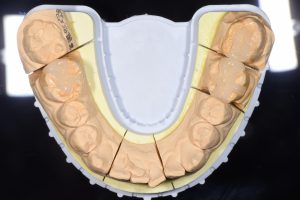

完成したセラミックインレー